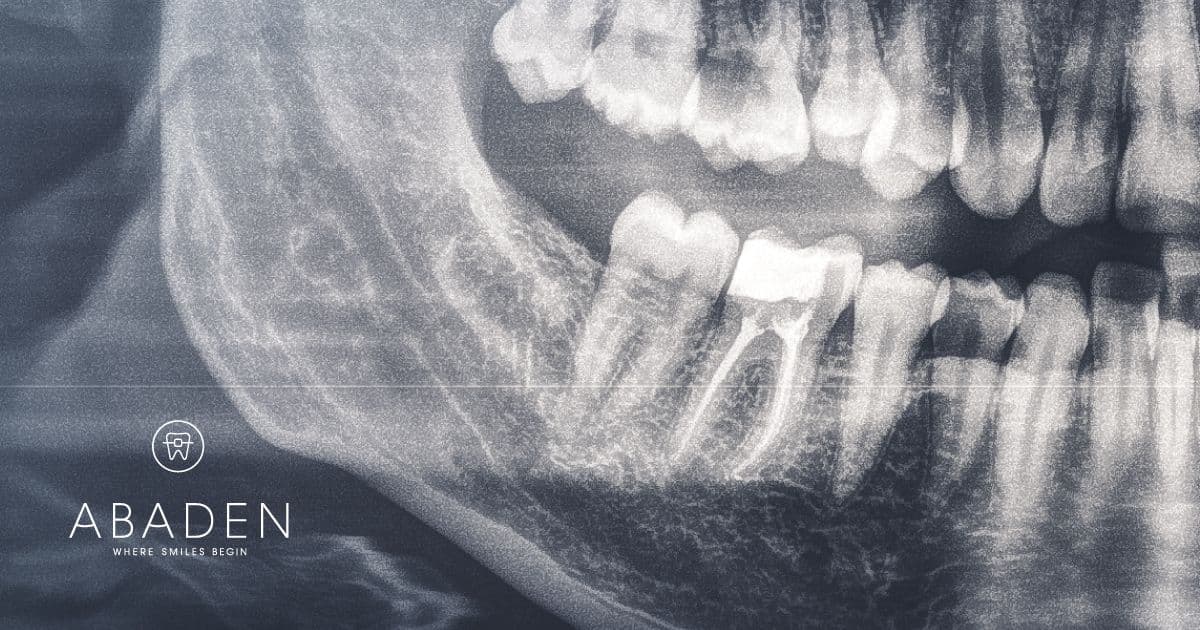

¿Qué es la fluorosis dental y cuál es su tratamiento?

En el ámbito de la odontología y la salud dental, seguro que muchas veces has escuchado lo beneficioso que es el flúor para prevenir las caries y fortalecer el esmalte. No obstante, el abuso y la exposición prolongada al fluoruro pueden causar un problema denominado fluorosis dental. ¿Qué es la fluorosis dental? La fluorosis dental … Leer más